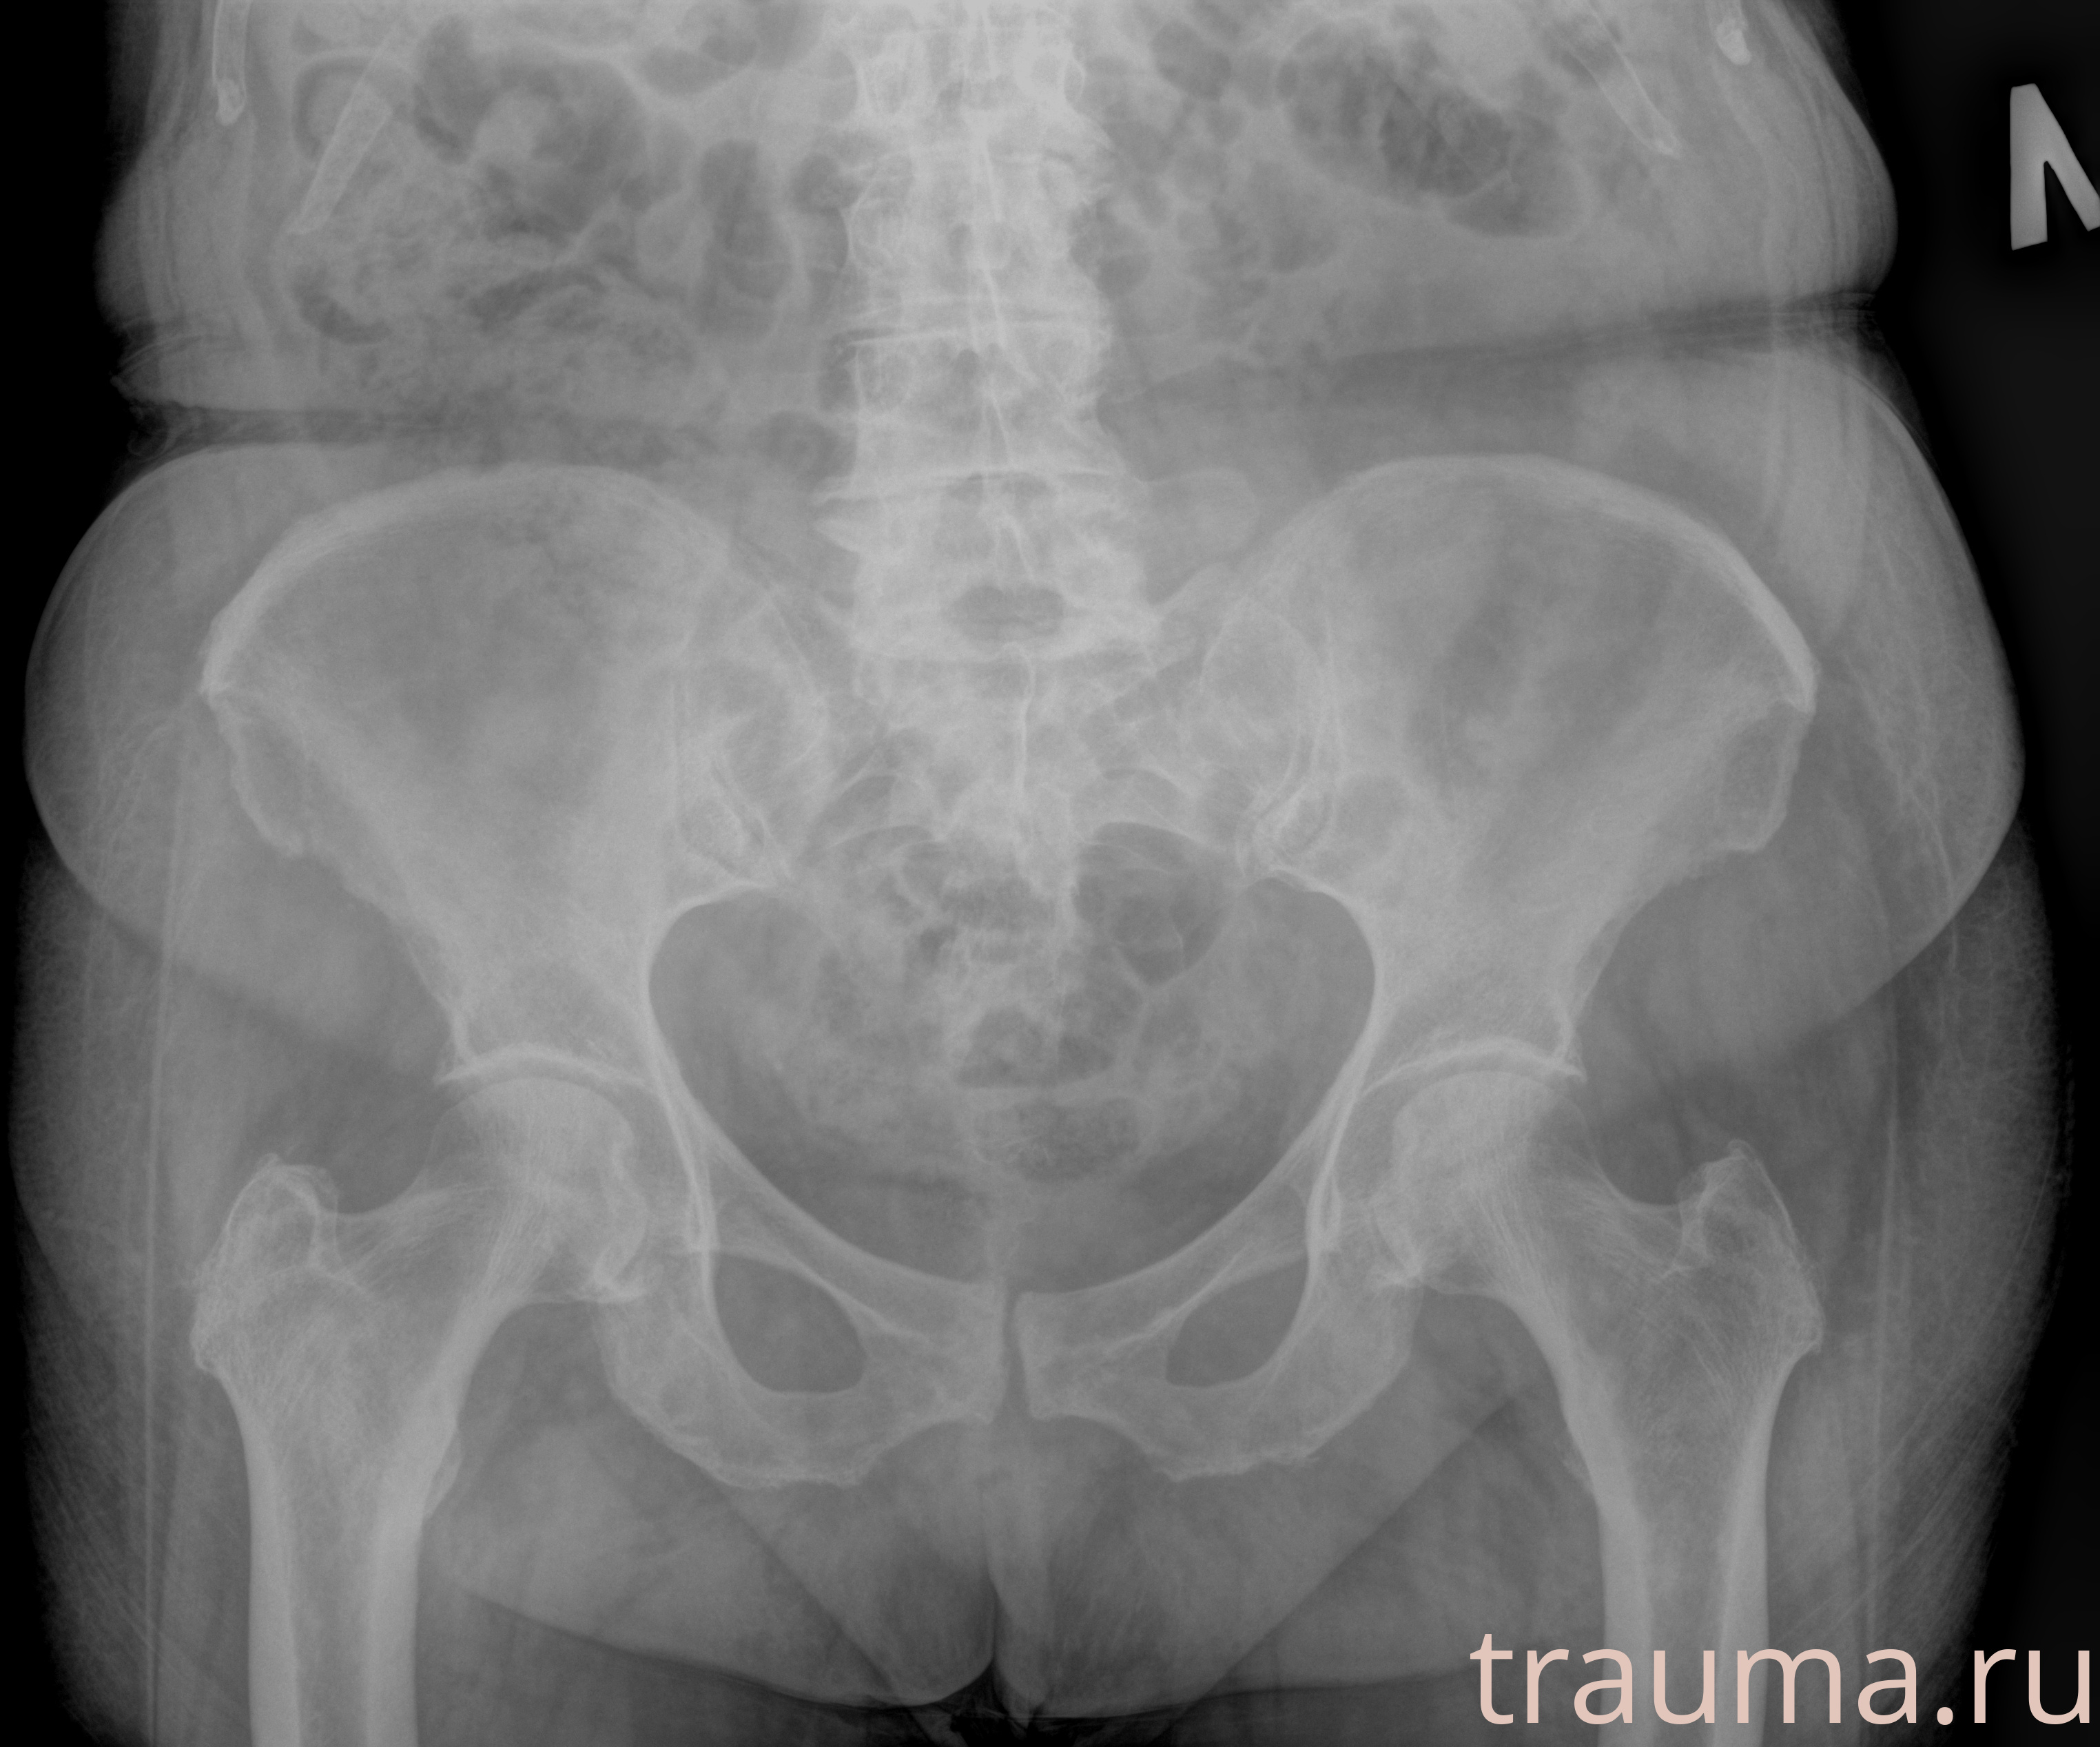

Рентген на дому: по вашему адресу приезжает врач-рентгенолог, травматолог-ортопед с мобильным рентгеновским аппаратом, проводит диагностику травмы или заболевания, делает необходимые рентгенограммы, дает рекомендации по дальнейшему лечению. Получить качественные снимки в домашних условиях возможно благодаря уникальной методике, разработанной МосРентген Центром для института  Склифосовского

при переломе шейки бедра и пневмонии от компании МосРентген Центр - партнера Института имени Склифосовского